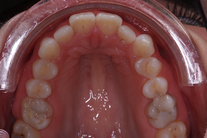

Tandreglering 4

40-årig kvinna som tycker att de två framtänderna står ut framför alla andra tänder. Behandlingen bestod av 11 månader med genomskinliga Invisalignskenor.